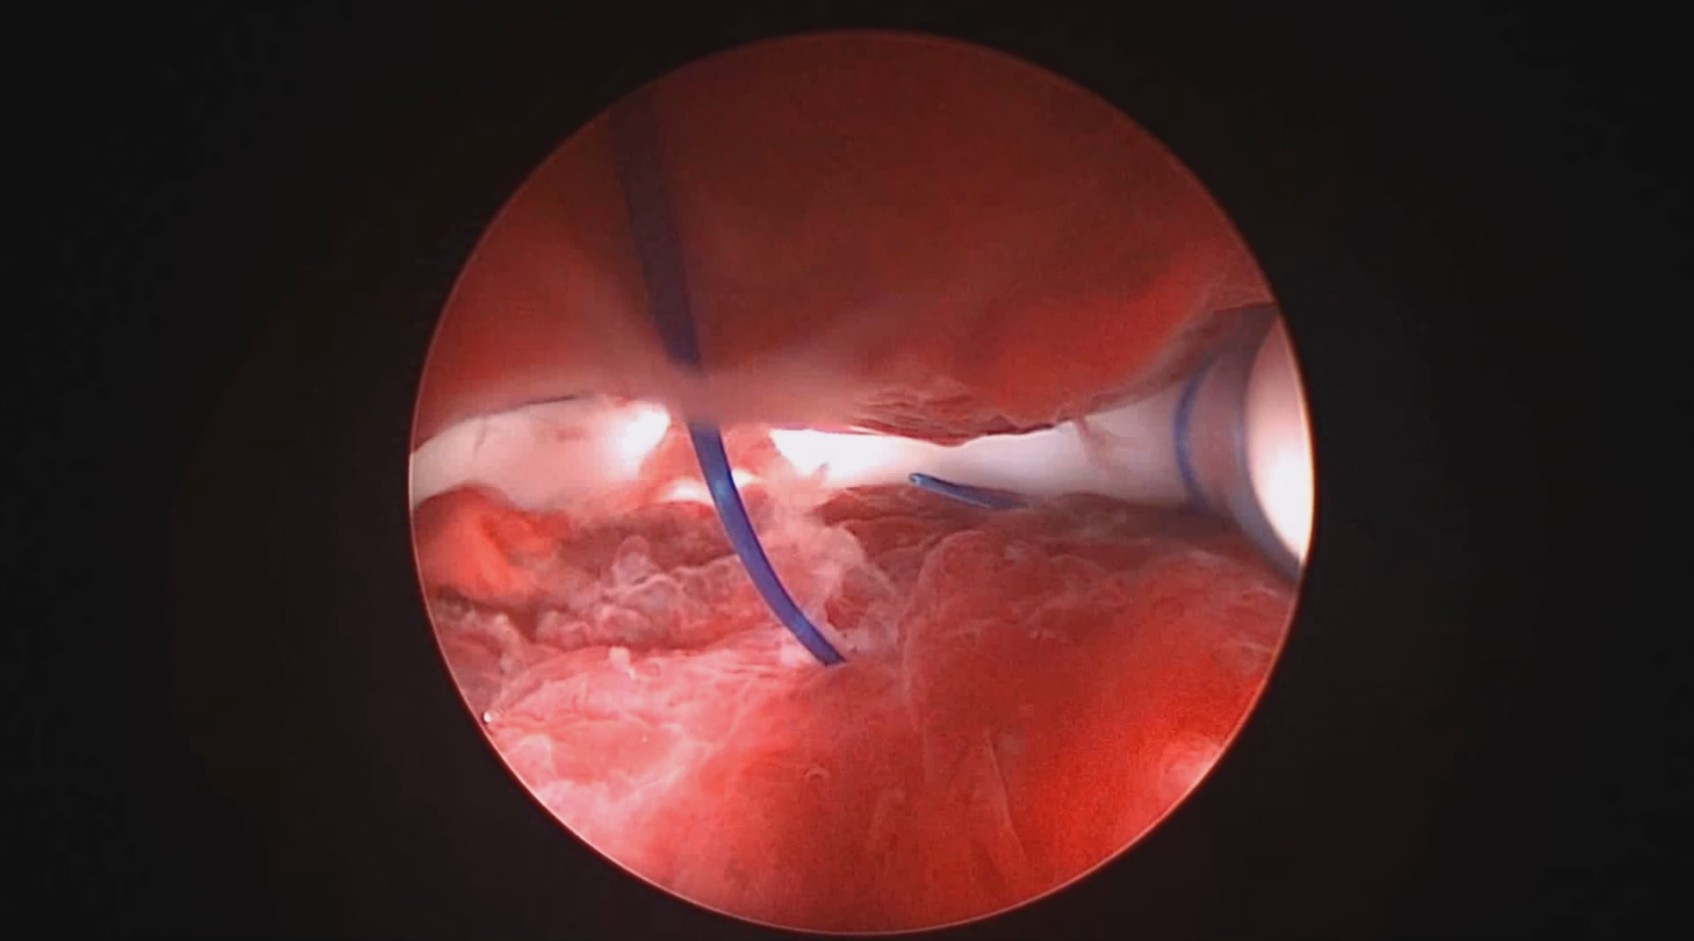

患者39岁,G4P2,顺产2次。2025年2月因异常子宫出血,阴道出血淋漓不净1+月行宫腔镜检查及内膜活检,病检为子宫内膜增生(无非典型)伴息肉形成。2025年3月,行经第3天,月经量大伴腹痛,要求放置曼月乐并固定。宫腔镜见内膜杂乱,脱落不全,吸刮内膜送病检,4-0不可吸收线将曼月乐环缝合固定于宫腔上段后壁。术中打结、推结很困难,放弃打结,留较长线尾在宫颈管,必要时可牵拉线尾调整节育环位置,只要缝合到子宫肌层,肌肉的卡压阻力可以起到固定作用,继续探索不用打结推结的固定方法。术后多次复查B超,子宫偏大,7.7cm*6.6cm*7.8cm,环顶端距宫底3cm。